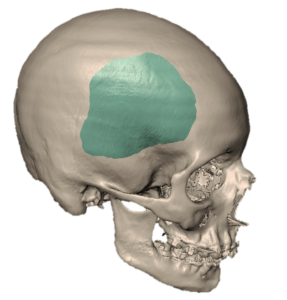

Los implantes son modelados y diseñados utilizando las imágenes obtenidas de una tomografía computarizada (Ctscan) o a partir de una resonancia magnética (MRI).

Posteriormente, se diseñan y fabrican los implantes con una extraordinaria precisión con una diferencia no mayor a 0.002 mm en un lapso no mayor de dos semanas.